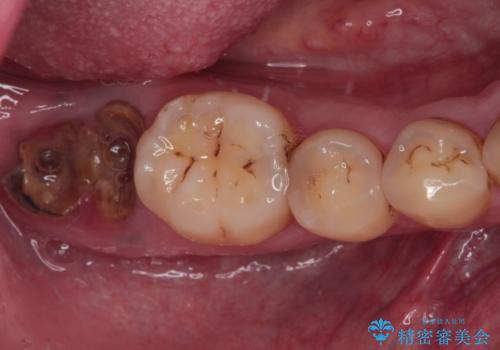

[ 歯槽堤保存術 ] [ 奥歯の破折 ] ソケットプリザベーションを併用したインプラント治療